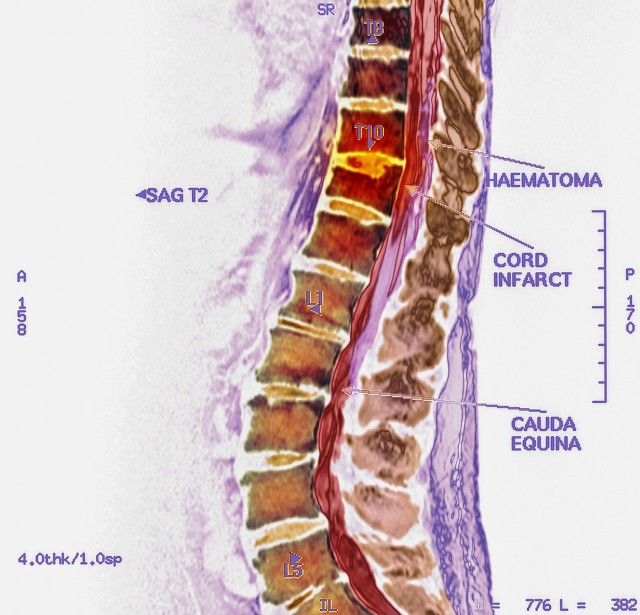

那位女家属说,我父亲腰部胀痛,下肢乏力活动不利,去市立医院看了,医生说是脊髓急性出血。

果然,市立医院的医生,那龙飞凤舞的字体间,依稀可以辨认出“脊髓出血”的诊断。

我知道这个疾病随时会加重,一旦出血量多了,会压迫脊髓神经,导致病人瘫痪可能,我只能一脸无奈地对那女家属说 “脊髓出血,这是很重的毛病啊,要随时注意观察病情发展的,严重的话,要马上手术治疗的,否则很有可能会瘫痪的!”

只见他神情严峻,紧缩双眉,半卧在床上,有气无力地说着; “医生,我两条腿没力气,站不起来了,小便好像也不是很畅通了。”

作为骨科医生,深刻了解脊髓神经细胞的脆弱性,神经有时甚至不用直接碰到,哪怕不小心隔着组织牵拉重了一点,敏感又脆弱的脊神经可能就会让肢体瘫痪掉,何况现在老头脊髓出血后压迫神经,已经如此之长的时间了。

脊髓血肿正压迫着神经细胞,大片细胞在慢慢坏死消亡,再不施救已无可挽回。

一周后,已经出现双下肢不能抬离床面了,小便只有靠导尿管解决了。

又是几天,老头双下肢已经彻底瘫痪了,小腿皮肤都有水肿的表现了。我告诉床位医生,这个病人一定要再给他签个告知协议书,讲清楚病情,别到时候发生纠纷。

手术中,发现老人脊髓血管有畸形,发生了血管瘤破裂出血,如果早日彻底检查,可以采用微创手术,脊髓减压治疗的,根本不用如此动如此大的开放手术。

如今脊髓出血产生的血肿,压迫神经已经日久,想要再恢复如初,真得要有神助了。